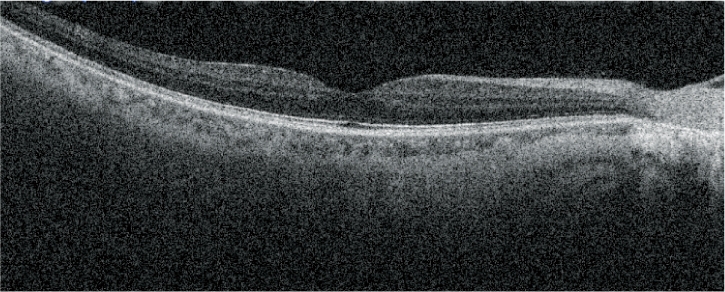

高清追蹤plus功能

高清追蹤plus功能可追蹤無意識(shí)的眼球運(yùn)動(dòng),在SLO圖像上保持相同的掃描位置,確保精確的圖像采集。此功能可獲得多至120張疊加的高清圖像。